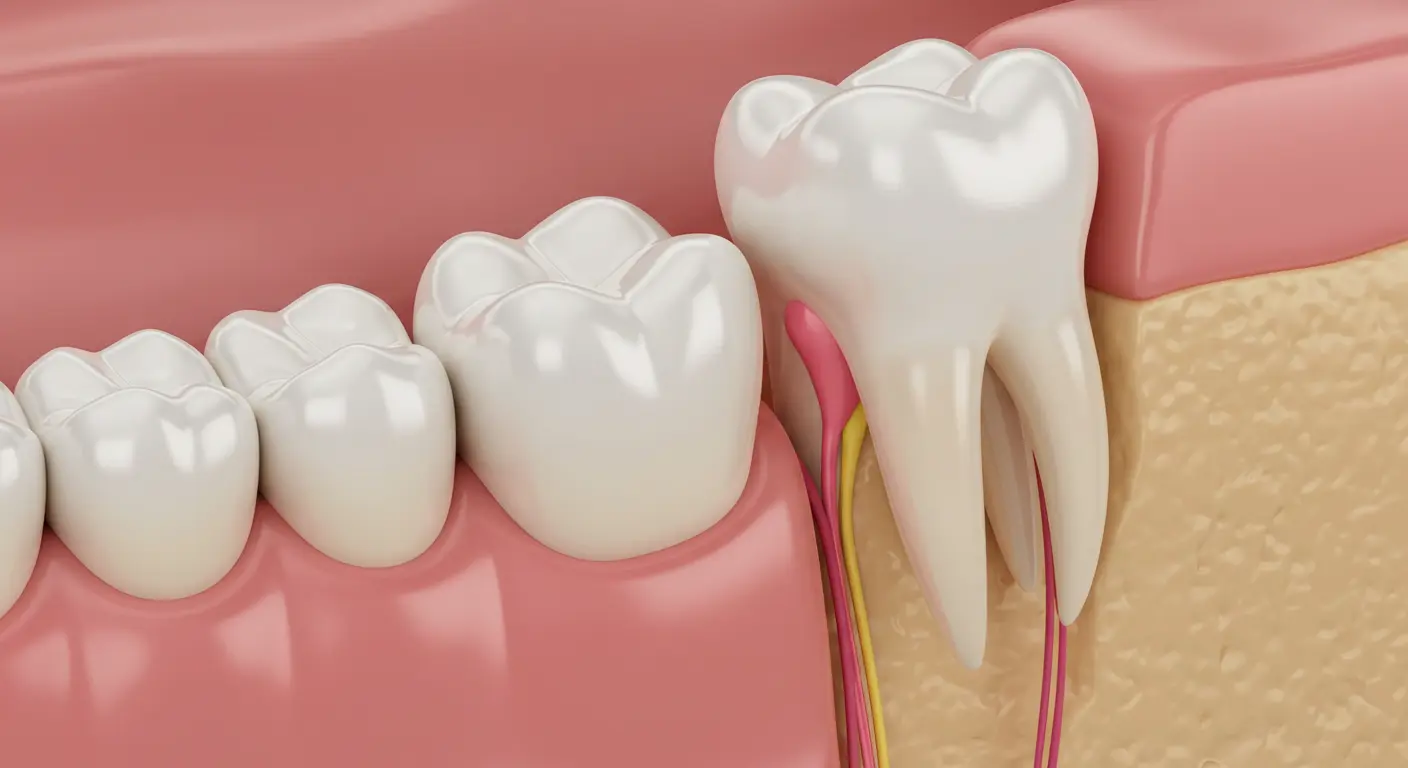

Impaction: When Teeth Can’t Erupt Properly

Impacted wisdom teeth are those that are blocked from fully emerging through the gum line. This can occur in various ways:

- Partial Impaction: Only a portion of the wisdom tooth breaks through, creating a flap of gum tissue that can trap food and bacteria, leading to infection.

- Full Bony Impaction: The wisdom tooth remains completely encased within the jawbone.

- Soft Tissue Impaction: The crown of the wisdom tooth has erupted through the bone but is still covered by gum tissue.

Damage to Adjacent Teeth: Pressure and Root Resorption

Misaligned or impacted wisdom teeth can exert pressure on the adjacent second molars. Over time, this pressure can cause damage to these healthy teeth, including:

- Cavities: Difficulty in cleaning around the wisdom teeth can increase the risk of decay in the adjacent molars.

- Root Resorption: In some cases, the pressure from the wisdom tooth can cause the roots of the neighboring tooth to resorb or dissolve.